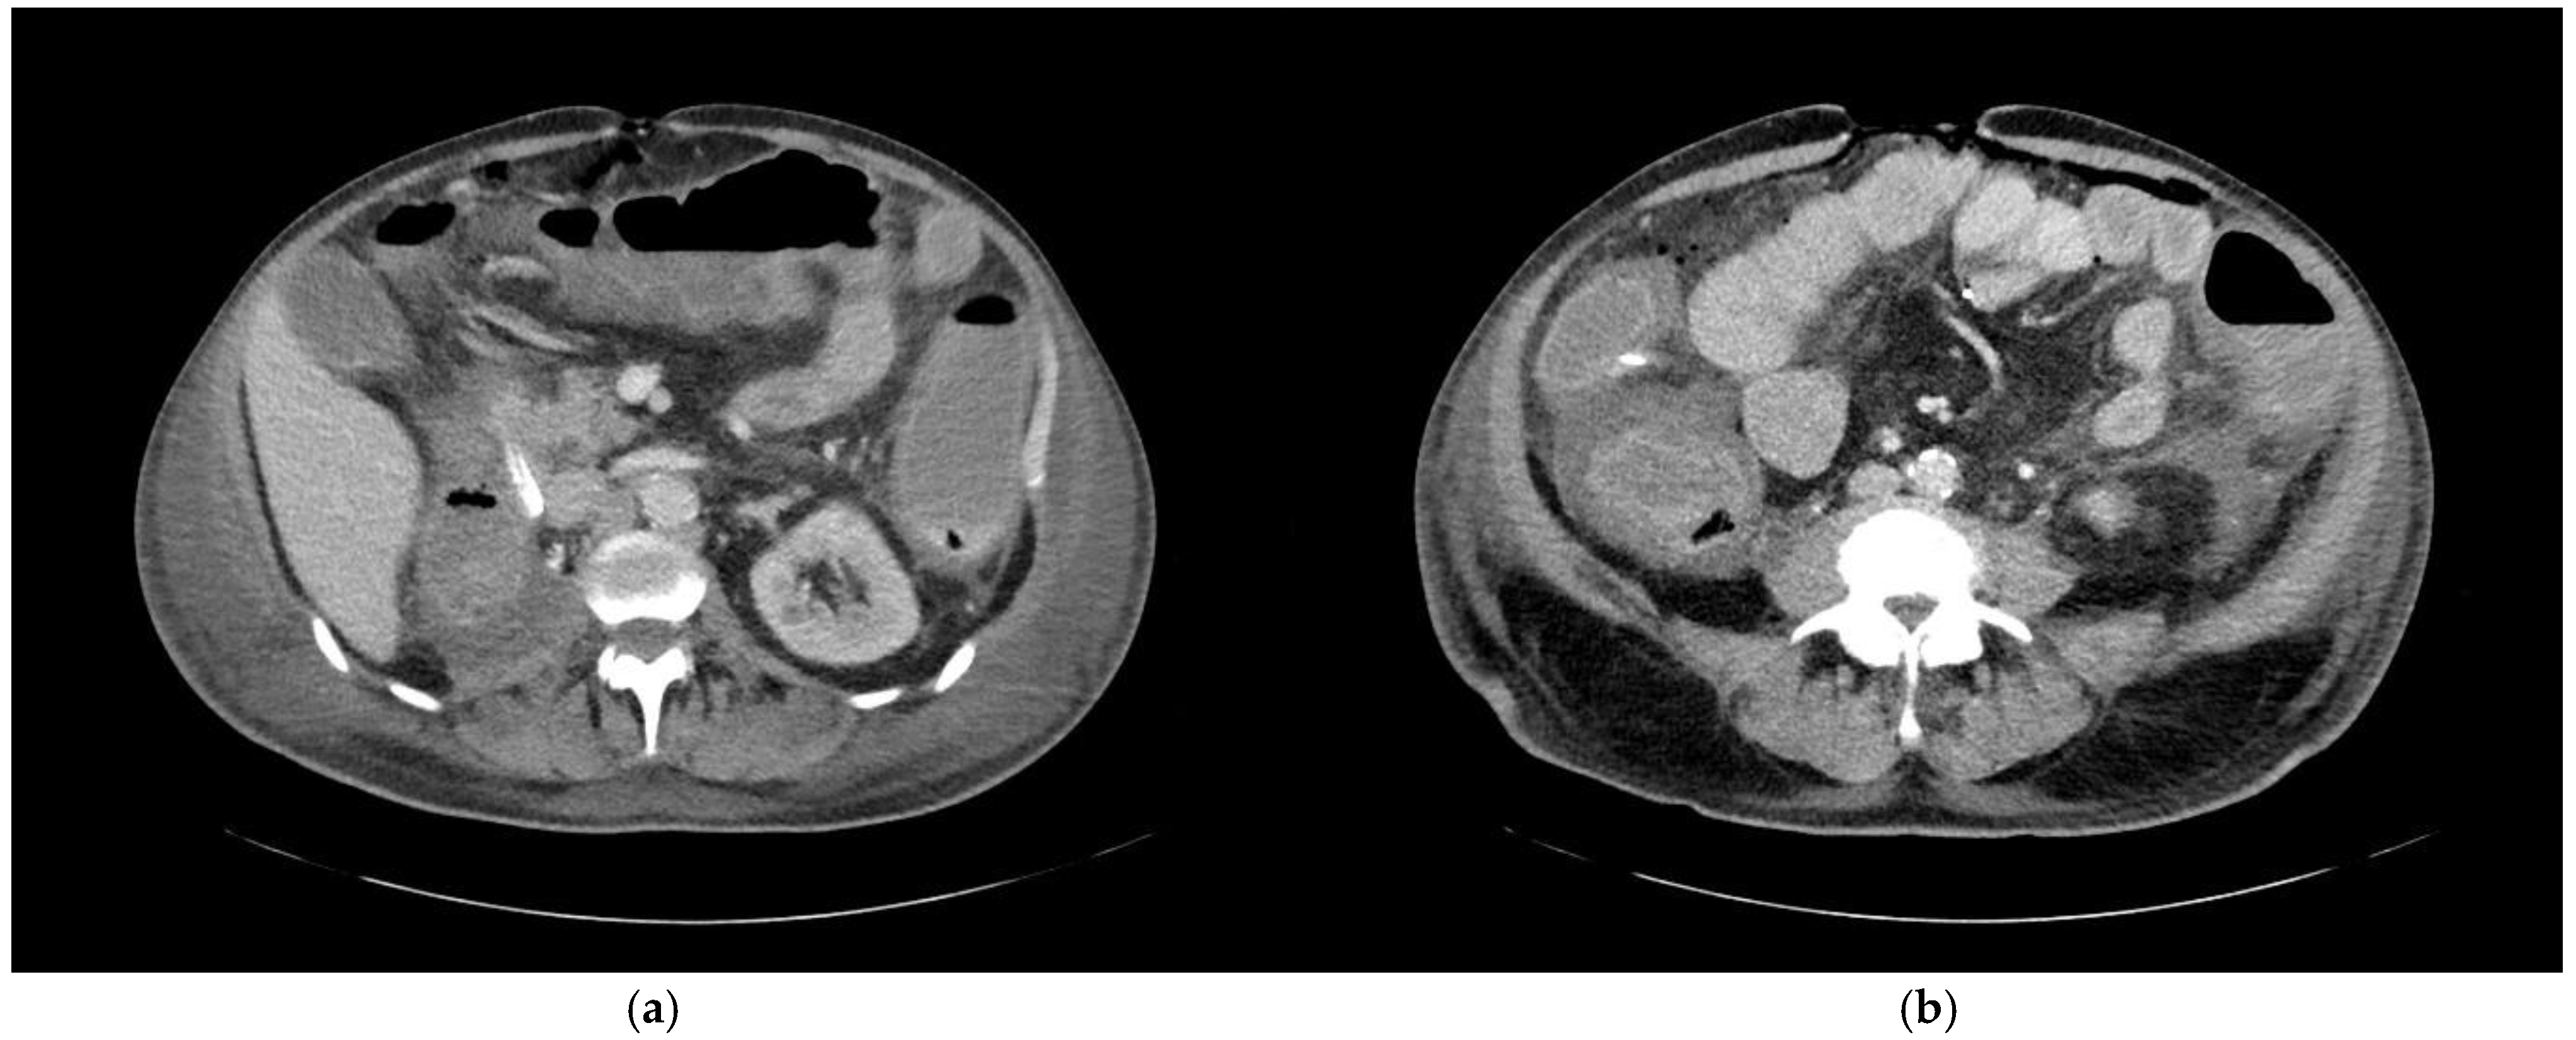

Abdominal foci were distributed across 16 distinct anatomical locations, with the colon identified as the most common site, harboring 14 foci (refer to Table 4 and Figure 4). Morphological analysis from imaging studies revealed that only 42.9% of these colonic findings were categorized as definite, reflecting some diagnostic ambiguity in distinguishing inflammatory conditions within this region. Following the colon, the pancreas and the small intestine were the next most frequent sites of inflammation, with 12 and 6 foci, respectively. Additionally, a single focus in the kidney was definitively identified, highlighting both the diversity and the varying levels of diagnostic clarity associated with abdominal foci.

Figure 4. A 68-year-old patient with an unknown focus of origin. CT morphologic signs of colitis include (a) circular colonic wall thickening and pericolic fat stranding, and (b) decreased mural contrast enhancement indicating intestinal wall edema and adjacent ascites.